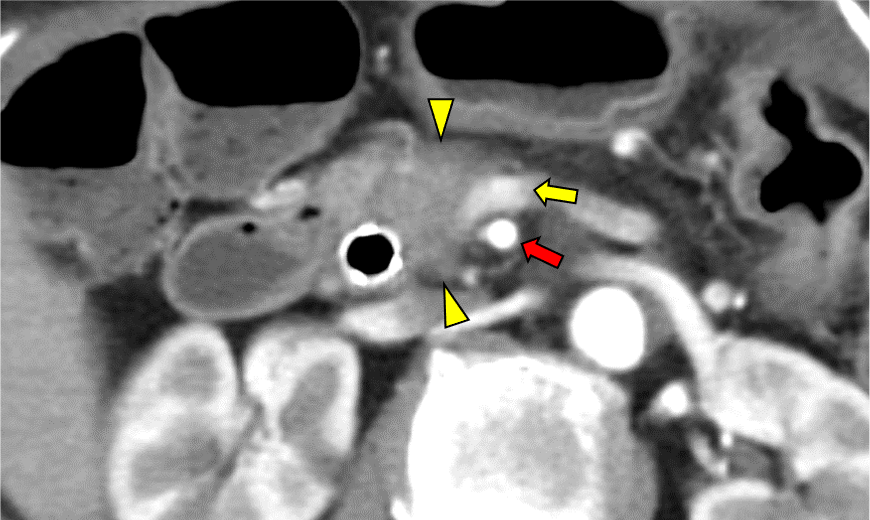

図3.造影CT 膵実質相 Axial像 70keV

膵頭部の膵癌病変(矢頭)は門脈 (矢印:黄)と半周を超える接触あり。上腸間膜動脈(矢印:赤)および、その他の主要な動脈との明らかな接触は認めなかった。